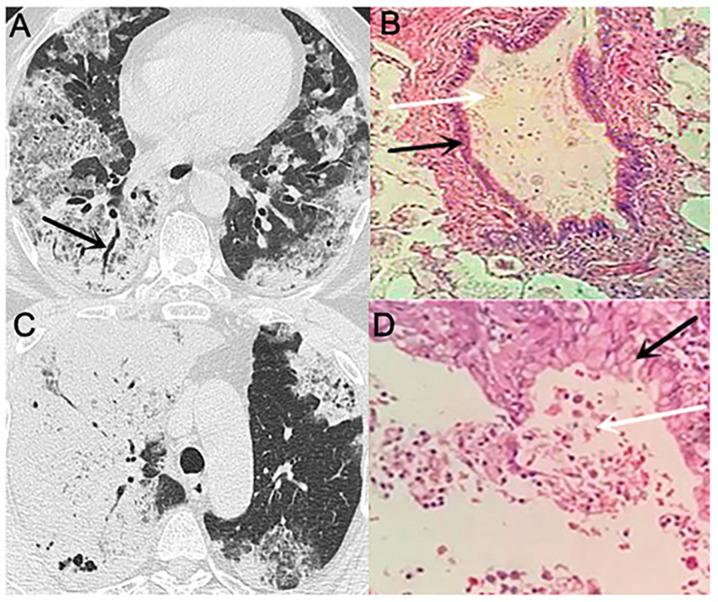

Patients with pneumonia-type lung cancer (PTLC) do not exhibit specific clinical features, which makes imaging diagnosis difficult. Therefore, the aetiology of the pathological changes occurring during PTLC remains unclear. The current study aimed to explore the possible mechanism of PTLC formation by CT scans and pathological analysis of the lungs. A retrospective analysis was conducted on the CT and pathological data of 17 cases of PTLC. The diagnosis of lung cancer was confirmed by pathology. The CT scans of nine patients indicated diffuse distribution of lesions in the lungs, whereas those of three patients indicated single-lung multi-leaf distribution, and those of the remaining five patients included single-leaf distribution. All patients demonstrated increased plaque or patchy density in the majority of the lesions located near the heart. The pathological types of the identified tumours were mucinous adenocarcinoma with adherent growth as the main sub-type. A large number of mucus lakes were observed, containing floating tumour cells, as determined by optical microscopy. In addition, a number of tumour cells were located in the residual alveolar wall of the observed mucus lakes. The results of the present study suggested that the mucinous adenocarcinoma tumour cells produced substantial quantities of mucus, and that the cells were scattered and planted along with the mucus through the airway, which led to possible development of pneumonia-type mucinous adenocarcinoma.